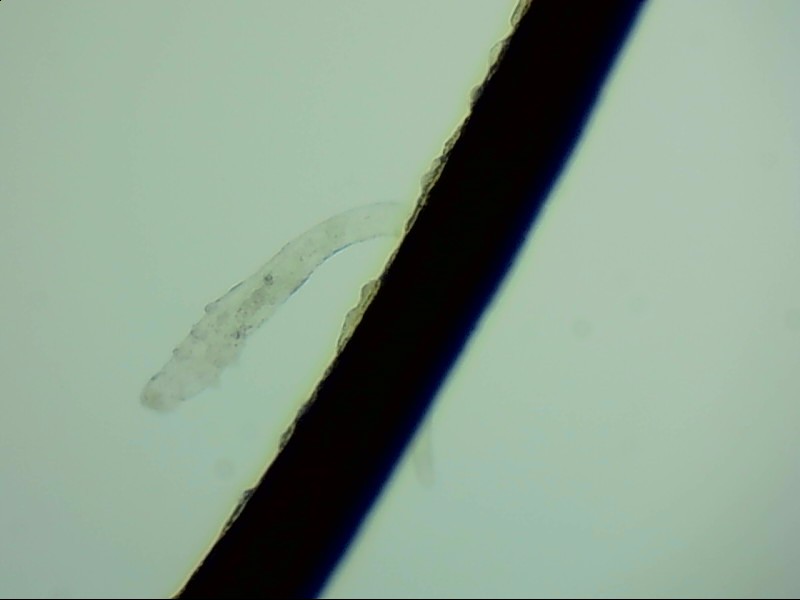

螨蟲怎么會(huì)爬到睫毛里?廈門眼科中心蠕形螨性瞼緣炎門診張麗穎博士后介紹,人體螨蟲主要有兩種,一種是皮脂螨,主要寄生于皮脂腺和瞼板腺內(nèi);另一種是蠕形螨,“住”在睫毛毛囊里,晚上從毛囊里爬出來,白天躲在毛囊里產(chǎn)卵。

蠕形螨可吞噬脂質(zhì),引起干眼。蠕形螨性瞼緣炎最常見的癥狀就是眼睛干癢、眼屎增多、眼瞼紅腫。這些癥狀與干眼癥和結(jié)膜炎很像,很容易被誤診。如果治療不及時(shí),病情嚴(yán)重會(huì)誘發(fā)角結(jié)膜炎,還可能使視力受損。

據(jù)介紹,這種疾病確診主要通過觀察睫毛里的螨蟲數(shù)量聯(lián)合瞼緣及眼表情況共同診斷。一般而言,如果12根睫毛里,有2條或是超過2條的螨蟲就可以被確診。如果檢查確實(shí)發(fā)現(xiàn)較多的蠕形螨感染,建議加上抗螨治療。張麗穎說,發(fā)現(xiàn)眼睛干澀、發(fā)癢,不要自行用藥,建議到醫(yī)院就診。如果長期反復(fù)多發(fā)霰粒腫,要考慮是否存在蠕形螨感染。